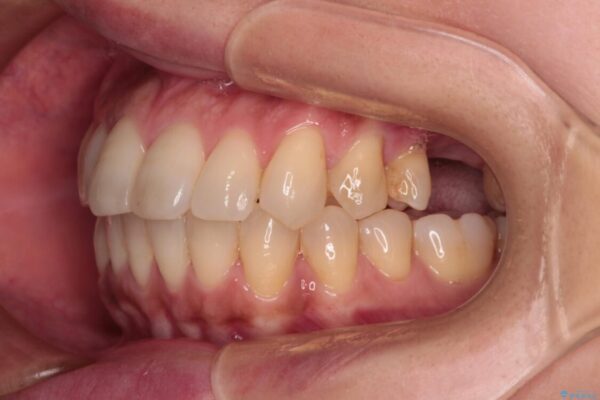

左上第一大臼歯を抜歯した際に、スペースを閉じたそうですが、歯が傾斜してものが挟まって不快とのことでした。

インビザライン矯正で全体の歯列と整えるとともに、左上第一大臼歯部にはスペースを作り、インプラントによる補綴治療を行うこととしました。

治療後について

歯の傾斜が改善され、インプラントによるクラウンが装着されたことで、物が挟まることもなくなりました。

治療後

• インビザラインによる矯正治療と奥歯のインプラント治療 治療後画像